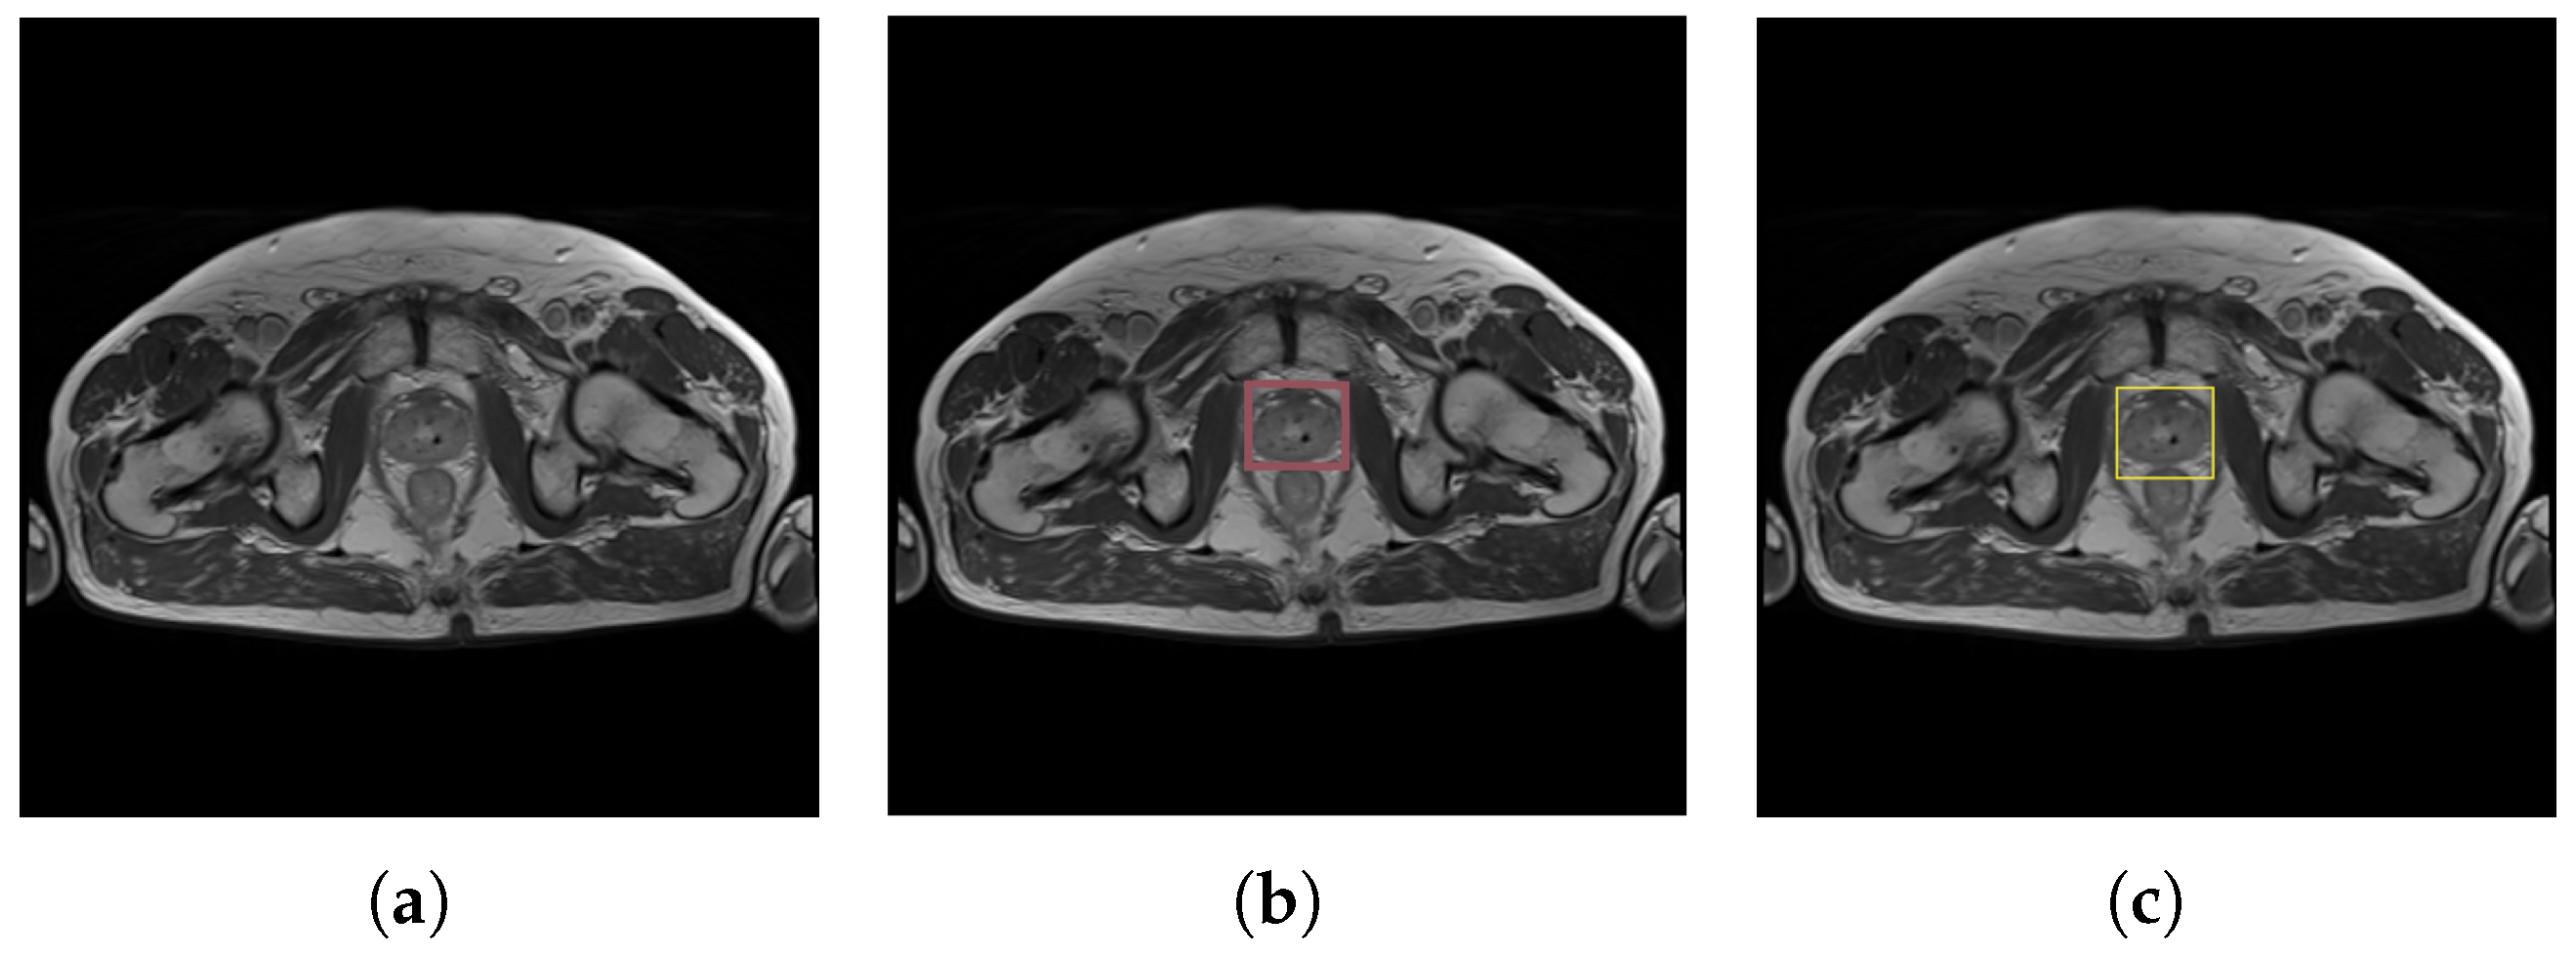

Two experiments were carried out in the first phase:

- Onefold modality (MRI)—The first experiment examined the performance of a model trained only on an MRI dataset. The dataset contains 666 training and 73 validation images. In Figure 6, the example validation image compares the predicted bounding box with the ground truth bounding box on the example validation image.

Figure 6. MRI results for prostate detection: (a) original prostate image, (b) ground truth bounding box, and (c) predicted bounding box. - Multimodal medical imagining (MRI and CT)—The training dataset was enlarged by adding CT scans. This approach was used to verify whether generalization is appropriately fitted to varying MRI data. The second experiment was based on 739 MR and 751 CT mixed images, where the validation dataset totals 149 images.